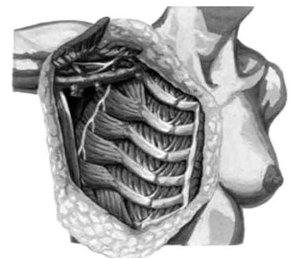

לאחר מכן כורתים את שריר החזה הגדול והקטן (Minor and major pectoralis). פותחים את בית השחי וכורתים את בלוטות הלימפה בשלושת האזורים של בית השחי (איור 24.12).

הגבולות האנטומיים של בית השחי, לצורך ניתוח זה, הם: מאחור - שריר הגב הרחיב (Latissimus dorsi) והשריר התת-שכמי (Subscapularis); מדיאלית - שריר המשור הקדמי (Serratus anterior) וצלעות בית החזה; מלפנים - שרירי הפקטורליס; ומעל - הווריד האקסילרי ממקום כניסתו לזרוע ועד האפקס של האקסילה שהוא אזור המעבר של הווריד האקסילרי מעל צלע 1 ומתחת לעצם הבריח. כל הבלוטות הנמצאות בתחום זה, כולל כלי הדם היוצאים מהווריד האקסילרי, נכרתות. בסיום כריתה זו מכסים את אזור הדיסקציה בשני מתלי העור, שהוכנו בזמן כריתת רקמת השד, ונתפרים ראשונית (איור 25.16 ותמונה 38.12).